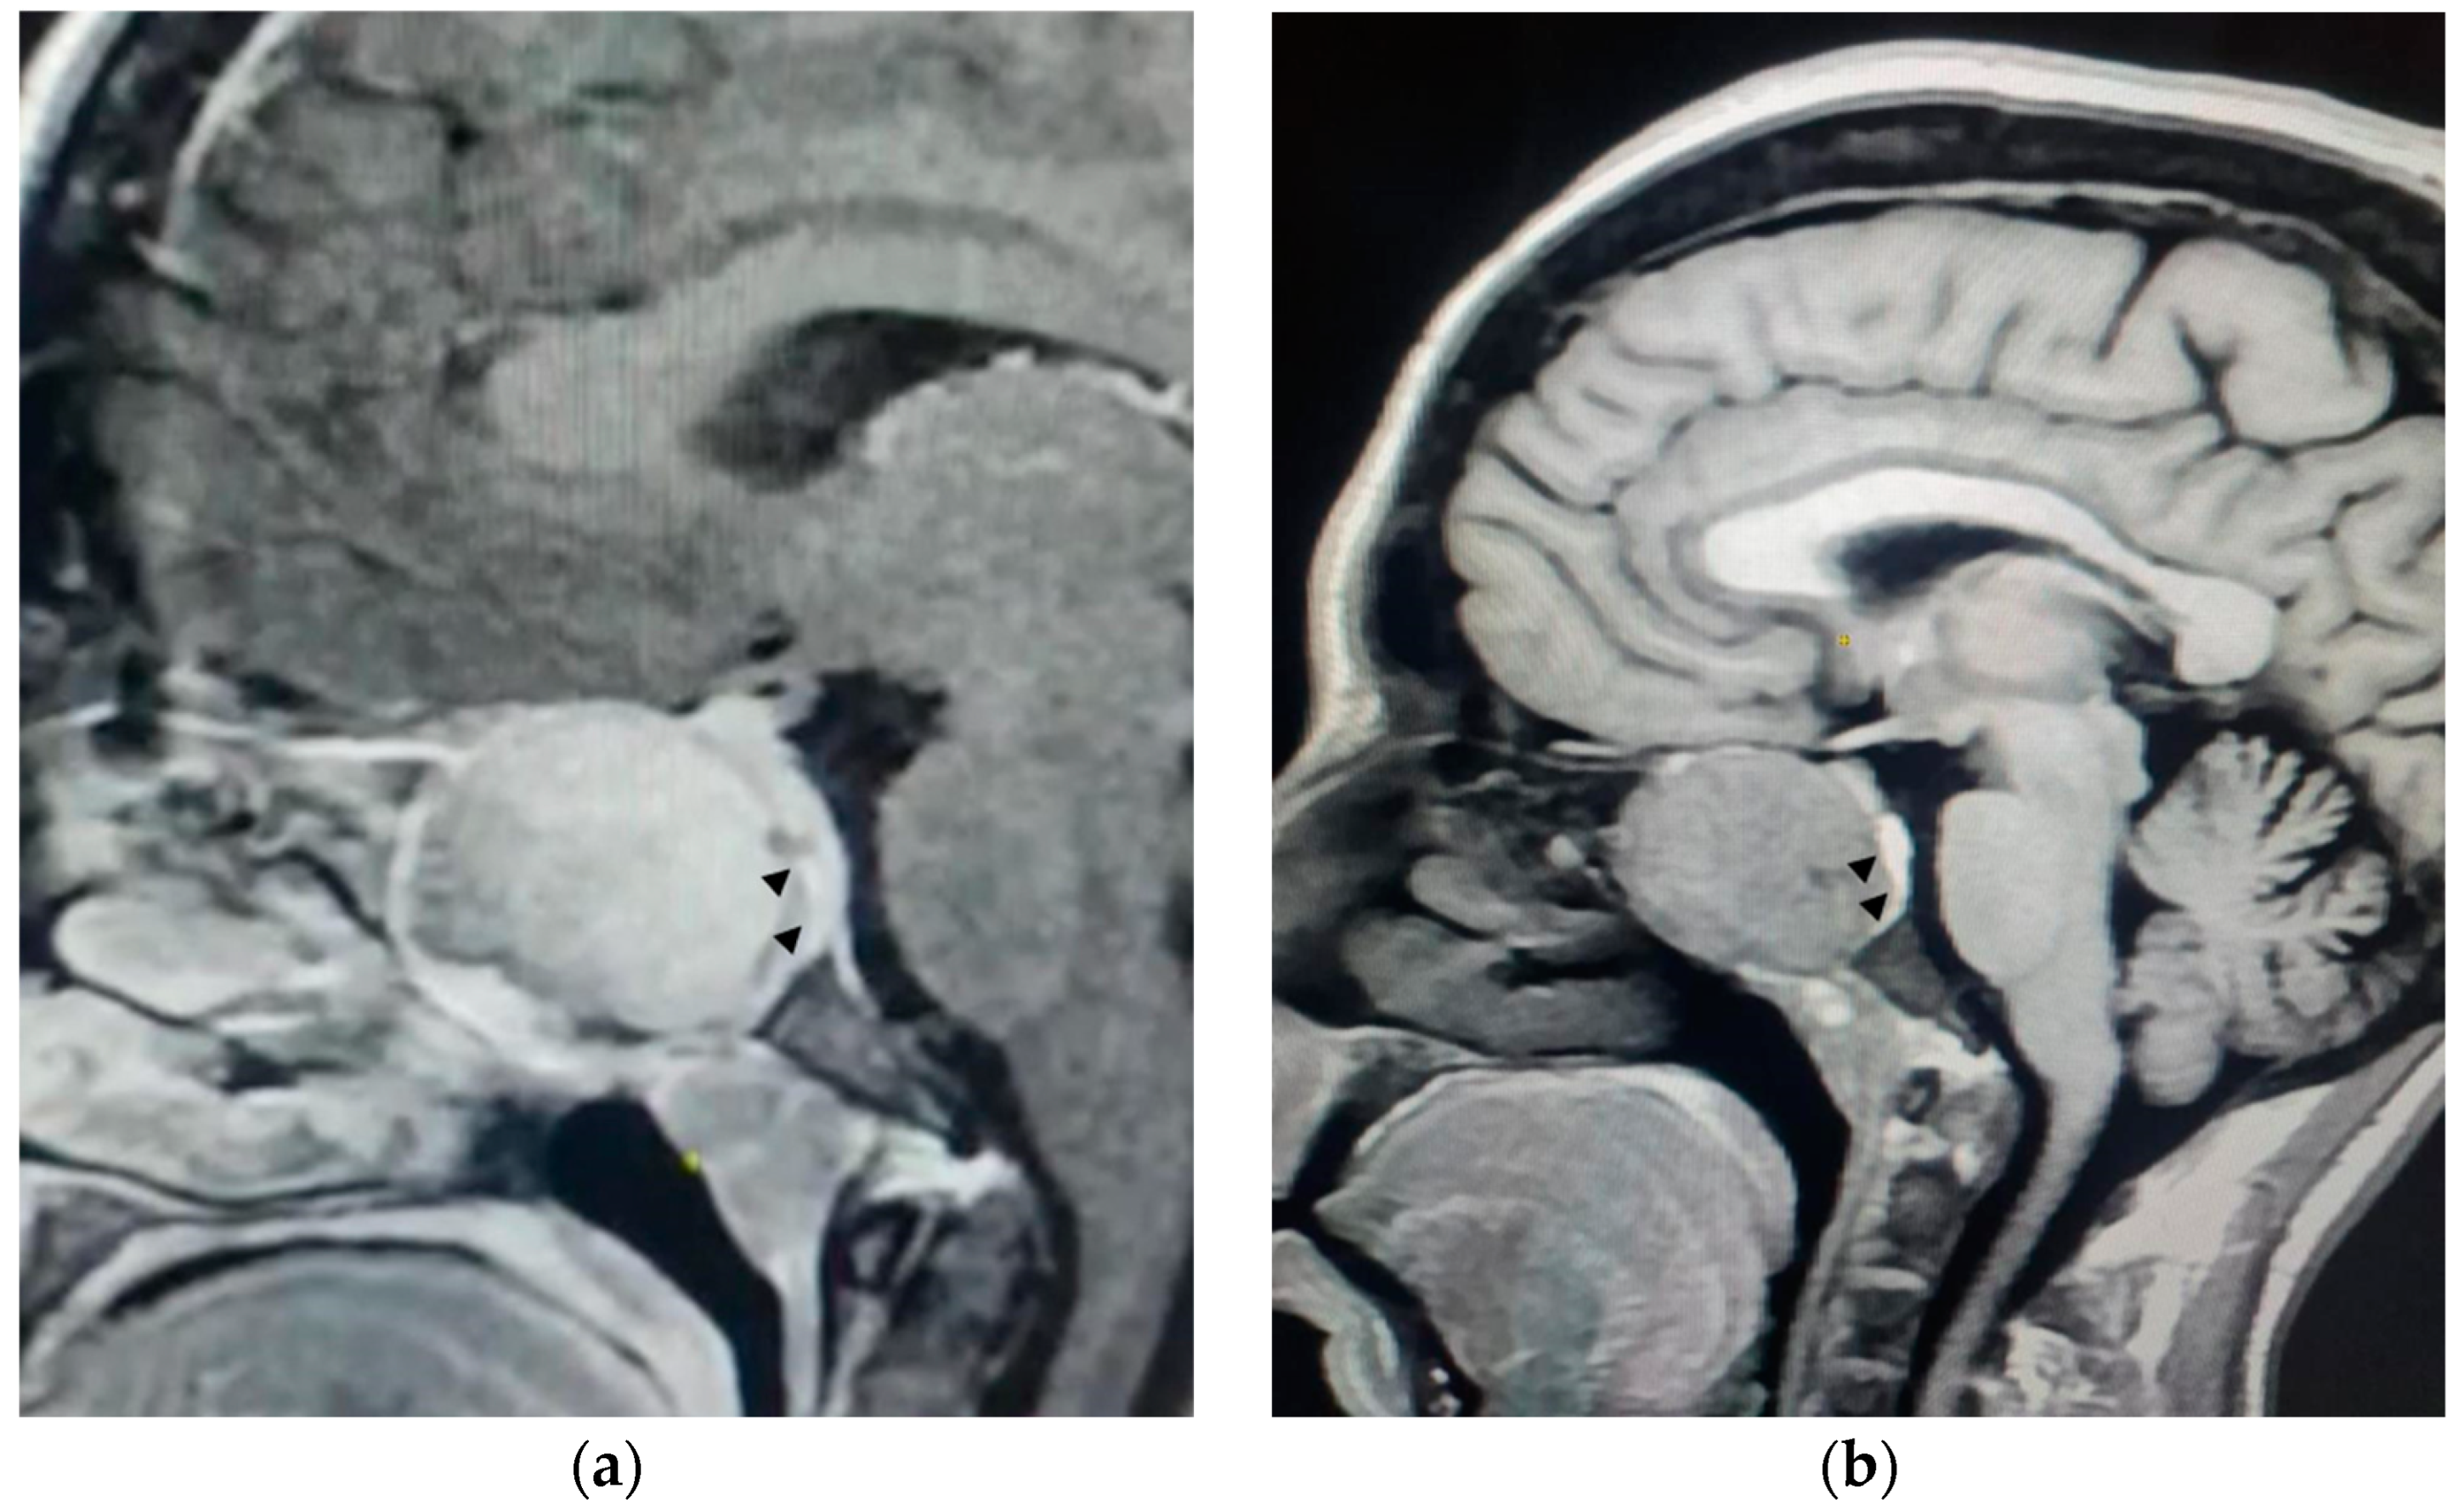

Magnetic resonance imaging (MRI) of the brain demonstrated a lesion centered in the sphenoid sinus, expanding the bony cortex of the sinus, which displaces the flattened pituitary gland posteriorly (Figure 1). Ultrasonography of the parathyroid glands revealed no abnormality. These findings were considered compatible with a sphenoid sinus brown tumor secondary to hyperparathyroidism.

Figure 1.

(a) A T1-weighted sagittal MRI with a gadolinium injection confirms the tissue nature of the mass and its expansion against the bony cortex (arrowheads). (b) A T1-weighted sagittal MRI without a gadolinium injection shows a lesion centered on the sphenoid sinus, expanding the bony cortex of the sinus, displacing the flattened pituitary gland posteriorly, filling the opto-chiasmatic cisterns superiorly, and making intimate contact with the optic nerve.

The imaging findings were critical in confirming the diagnosis of a brown tumor. The lesion’s location in the sphenoid sinus and its impact on surrounding structures, such as the pituitary gland and optic nerve, explained the patient’s visual symptoms and highlighted the need for prompt intervention.